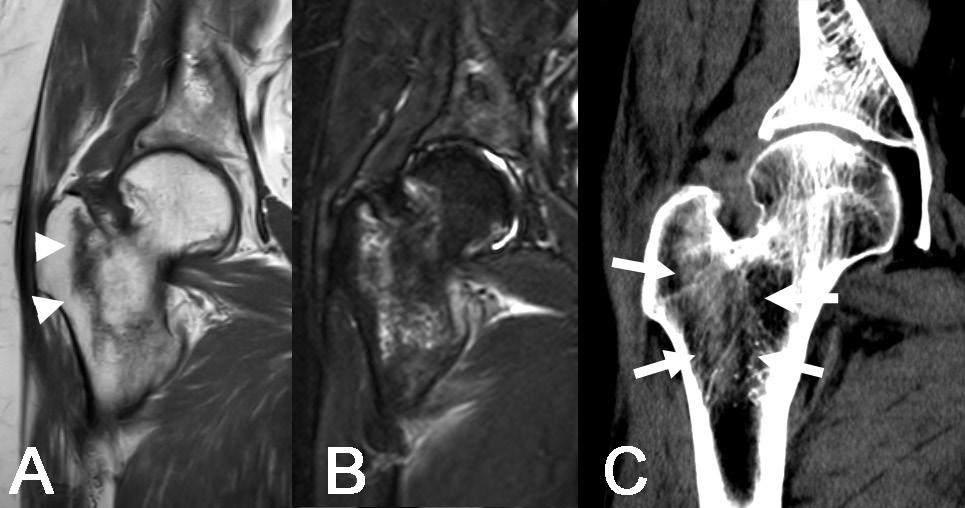

Användningen av DWI (Bild 1) skulle kunna minska behovet av kontrastmedel vid kontrollundersökningar efter tumöroperationer eftersom dagens diagnostik med konventionella MR-sekvenser till stor del bygger på bedömning av kontrastmedelsuppladdning i suspekta vävnader. DWI har dock sina begränsningar, bland annat på grund av magnetfältets inhomogenitet i ojämna områden av vår kropp (till exempel området kring axelleden där det finns en disproportion mellan dimensionerna av nacken och axlarna samt närvaron av rörliga lungor, stora kärl etc.) vilket leder till tex bildförvrängningar och artefakter. Diffusion är en känslig metod, men dess användning inom rörelseapparatens system är för närvarande inte stor, eftersom det saknas studier på större material.

Diffusion tensor imaging (DTI), (Bild 2) är en variant av DWI som syftar till att avbilda den riktningsberoende signalen hos vattenmolekylernas diffusion i vävnaden. Inom rörelseapparaten kan DTI används för att avbilda diffusionen längs muskelfibrer9 för att bedöma skador på muskler som inte är synliga i konventionella sekvenser, vilket kan vara av betydelse för att upptäcka mindre, interna muskelskador hos idrottare.10,11 I utredningen av tumörer i, eller i anslutning till, nerver kan DTI används för att bedöma huruvida diffusionen längs med nerven är påverkad och därmed ge information om nervens integritet (Bild 2). Detta är relevant i differentialdiagnosen tex mellan nervtumörer och nervskidetumörer12 eller mellan lokalt växande och infiltrativa tumörer.13,14

Bild 1. En 20-årig patient med en palpabel tumor i området kring höger höft (a - pilar). MRT visade en förändring med begränsad diffusion (b och c - streckad pil). Biopsi visade osteosarkom. a – Koronalt snitt, T2 Short Tau Inversion Recovery (STIR), b - Diffusionsviktad bild (b 800), c - Apparent diffusion coefficient.

Bild 2. En 55-årig patient med en palpabel tumör i hypothenarområdet. MRT bekräftar närvaron av en tumör i hypothenarregionen (a, b - pilar). På konventionella sekvenser (a - T1-viktad bild, b - T2-viktad bild) är differentiering mellan nervtumörer mycket svår. Diffusion tensor imaging (DTI) (c) visade att tumören inte påverkar diffusionen och att ulnarnervgrenarna ligger i tumörens periferi, vilket underlättar för kirurgen att avlägsna tumören. Radiologisk misstanke om schwannom bekräftades intraoperativt och histopatologiskt.